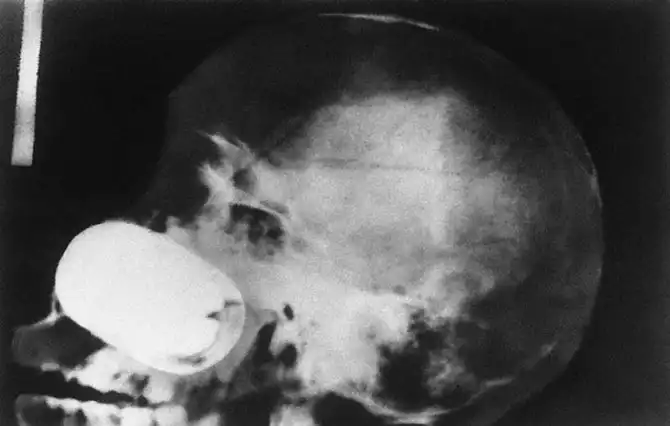

Граната в черепе заключенного.